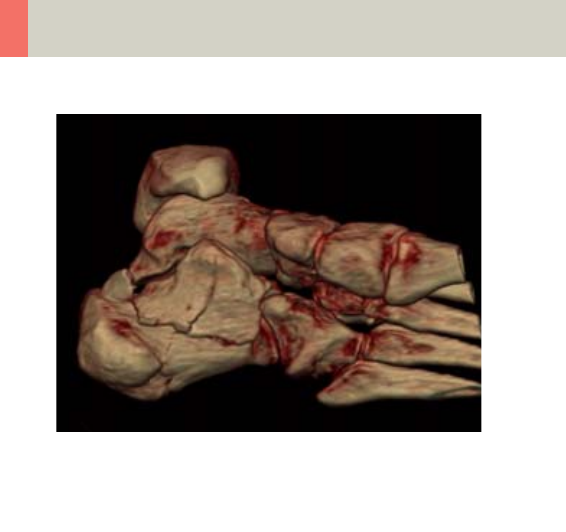

Lower Extremities 346

•Overview 346

- General Hints 348

- Body Kernels 349

•Scan Protocols 350

- Knee 350

- Foot 352

- ExtrRoutineHR 354

- ExtrCombi 358

12